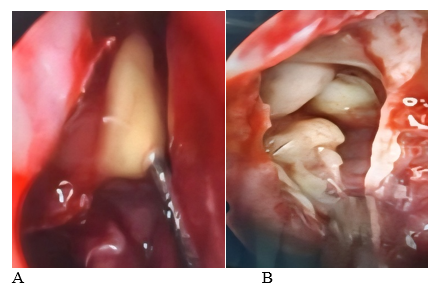

A 6-year-old female presented to the emergency department with a 72-hour history of fever and swelling of the right eyelid. Previous outpatient antibiotic treatment had failed (amoxicillin and ceftriaxone). Physical examination revealed periorbital erythema and edema, without any restriction of extraocular movements. Nasal endoscopy showed significant turbinate enlargement (inferior and middle) and purulent discharge from the right middle meatus. Laboratory results indicated a high white blood cell count (18.0 K/mm³) with a neutrophilic predominance (82%). The patient was admitted for intravenous antibiotics (meropenem, vancomycin) and steroid therapy. A CT scan of the paranasal sinuses revealed opacification of the frontal, ethmoid, and maxillary sinuses, with sphenoid mucosal inflammation. There was also obstruction of the osteomeatal complex, hypertrophy of the inferior and medial turbinates, and enlargement of the adenoids (Figure 1); there were no signs of intracranial extension. Based on these findings, a diagnosis of pansinusitis complicated by preseptal cellulitis was established.

Figure 1 CT scans (A; coronal, B; sagittal) show increased opacity in the frontal, ethmoid, maxillary, and sphenoid regions, along with blockage of the osteomeatal complex and enlargement of the adenoid.